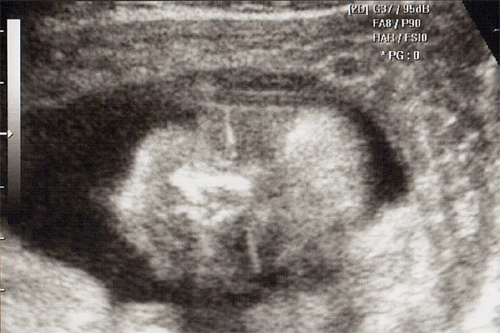

강아 ^^ 21주 강이의 정밀 초음파를 봤어 일반 초음파 보다는 더 정밀하게 나오더라구 엄청 커버린 강이가 한눈에 보이지 않을정도로 이제는 초음파 기계가 작아 보이더라..

강이 얼굴을 딱~ 보는순간.. 심장이 멈추고 코를 보는순가 다시 심장이 뛰기 시작했어 딱.. 아빠 코를 닮았더라 ^^:.. 이쁜자식...